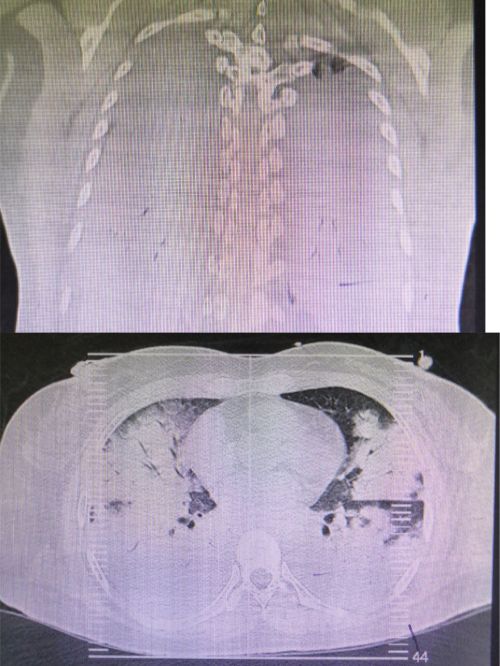

患者入院时肺部影像可见大片“白肺”。

复查肺部ct显示:肺部病变较前明显吸收改善。